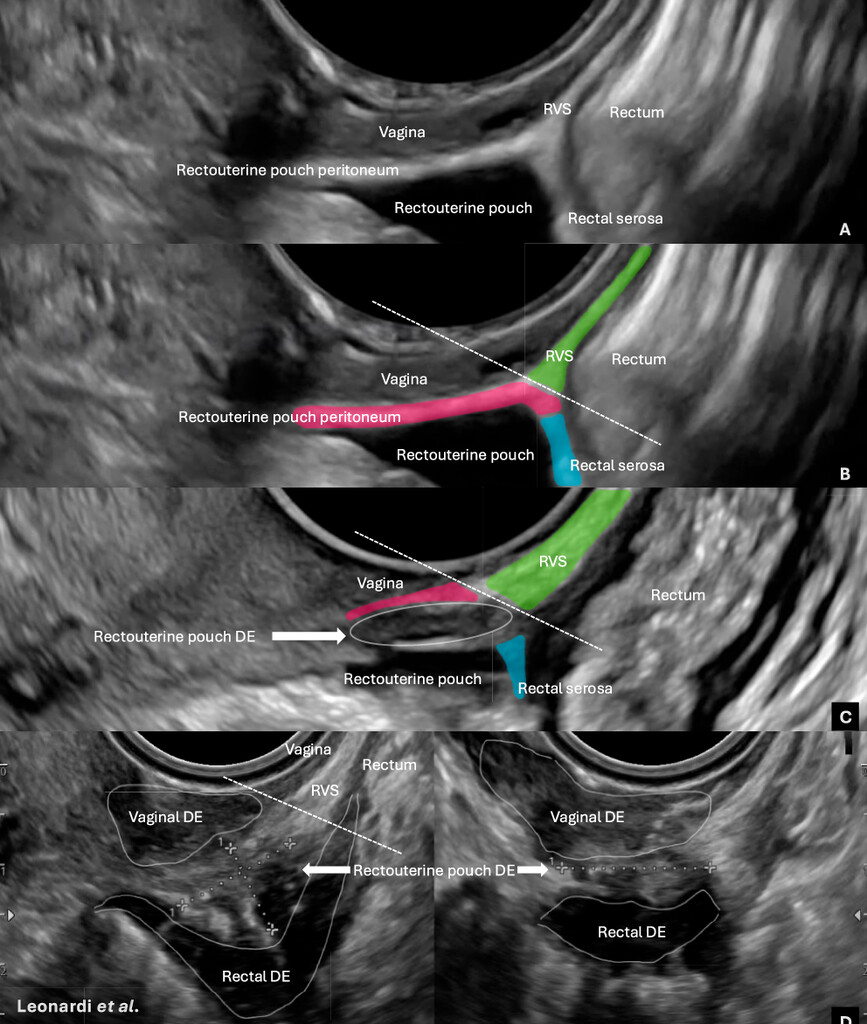

Posteriorni dio karlice umije biti anatomski izobličen endometriozom zbog adhezija, fibroza, zadebljanja i obliteracija rektouterinog prostora čini se da se lezija nalazi u septumu, a ona je zapravo iznad peritonealne refleksije ili na peritoneumu/ligamentima koji se tu anatomski lome. Dole se može vidjeti slika koja naglašava ovu optičku varku gdje ozbiljna duboka endometrioza daje privid centralne retroperitonealne lezije, iako je rektovaginalni septum suštinski očuvan, a lezije intrapertionealne ili na drugim, okolnim strukturama.

(C) Rektouterini prostor nije obliterisan (nema adhezija). Duboka endometrioza je prisutna u peritoneumu rektouterinog prostora, iznad i na peritonealnoj refleksiji, ali bez infiltracije u rektovaginalni septum.

(D) Teška duboka endometrioza posteriornog kompartmenta sa tri odvojena čvora (vagina, peritoneum rektouterinog prostora i intraperitonealni rektum). Adhezije između rektuma i vagine mogu stvoriti utisak da je centralna lezija “u retroperitoneumu”, ali pravilno razlikovanje peritonealne refleksije od rektovaginalnog septuma pokazuje da je septum u suštini očuvan i u najtežim slučajevima.